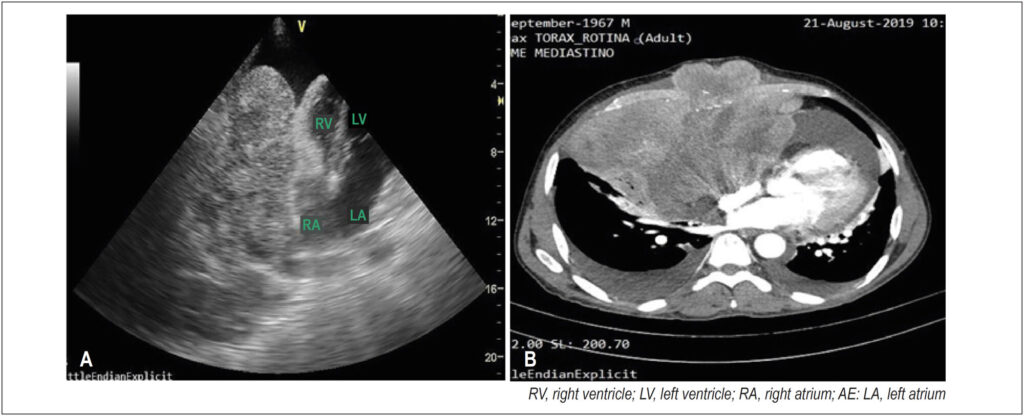

Echocardiographic Image of Primary Mediastinal Sarcoma with Pericardial Invasion

A 52-year-old man with signs and symptoms of cardiac tamponade underwent echocardiography of the right ventricle, which revealed significant pericardial effusion and an extensive heterogeneous mediastinal mass measuring approximately 15 × 8 cm in the pericardial space in close contact with the right chambers and causing diastolic collapse. The diagnostic hypothesis was a pericardial or mediastinal neoplastic process invading the pericardium. Subsequently, an immunohistochemical study confirmed a high-grade fusiform/pleomorphic cell sarcoma.